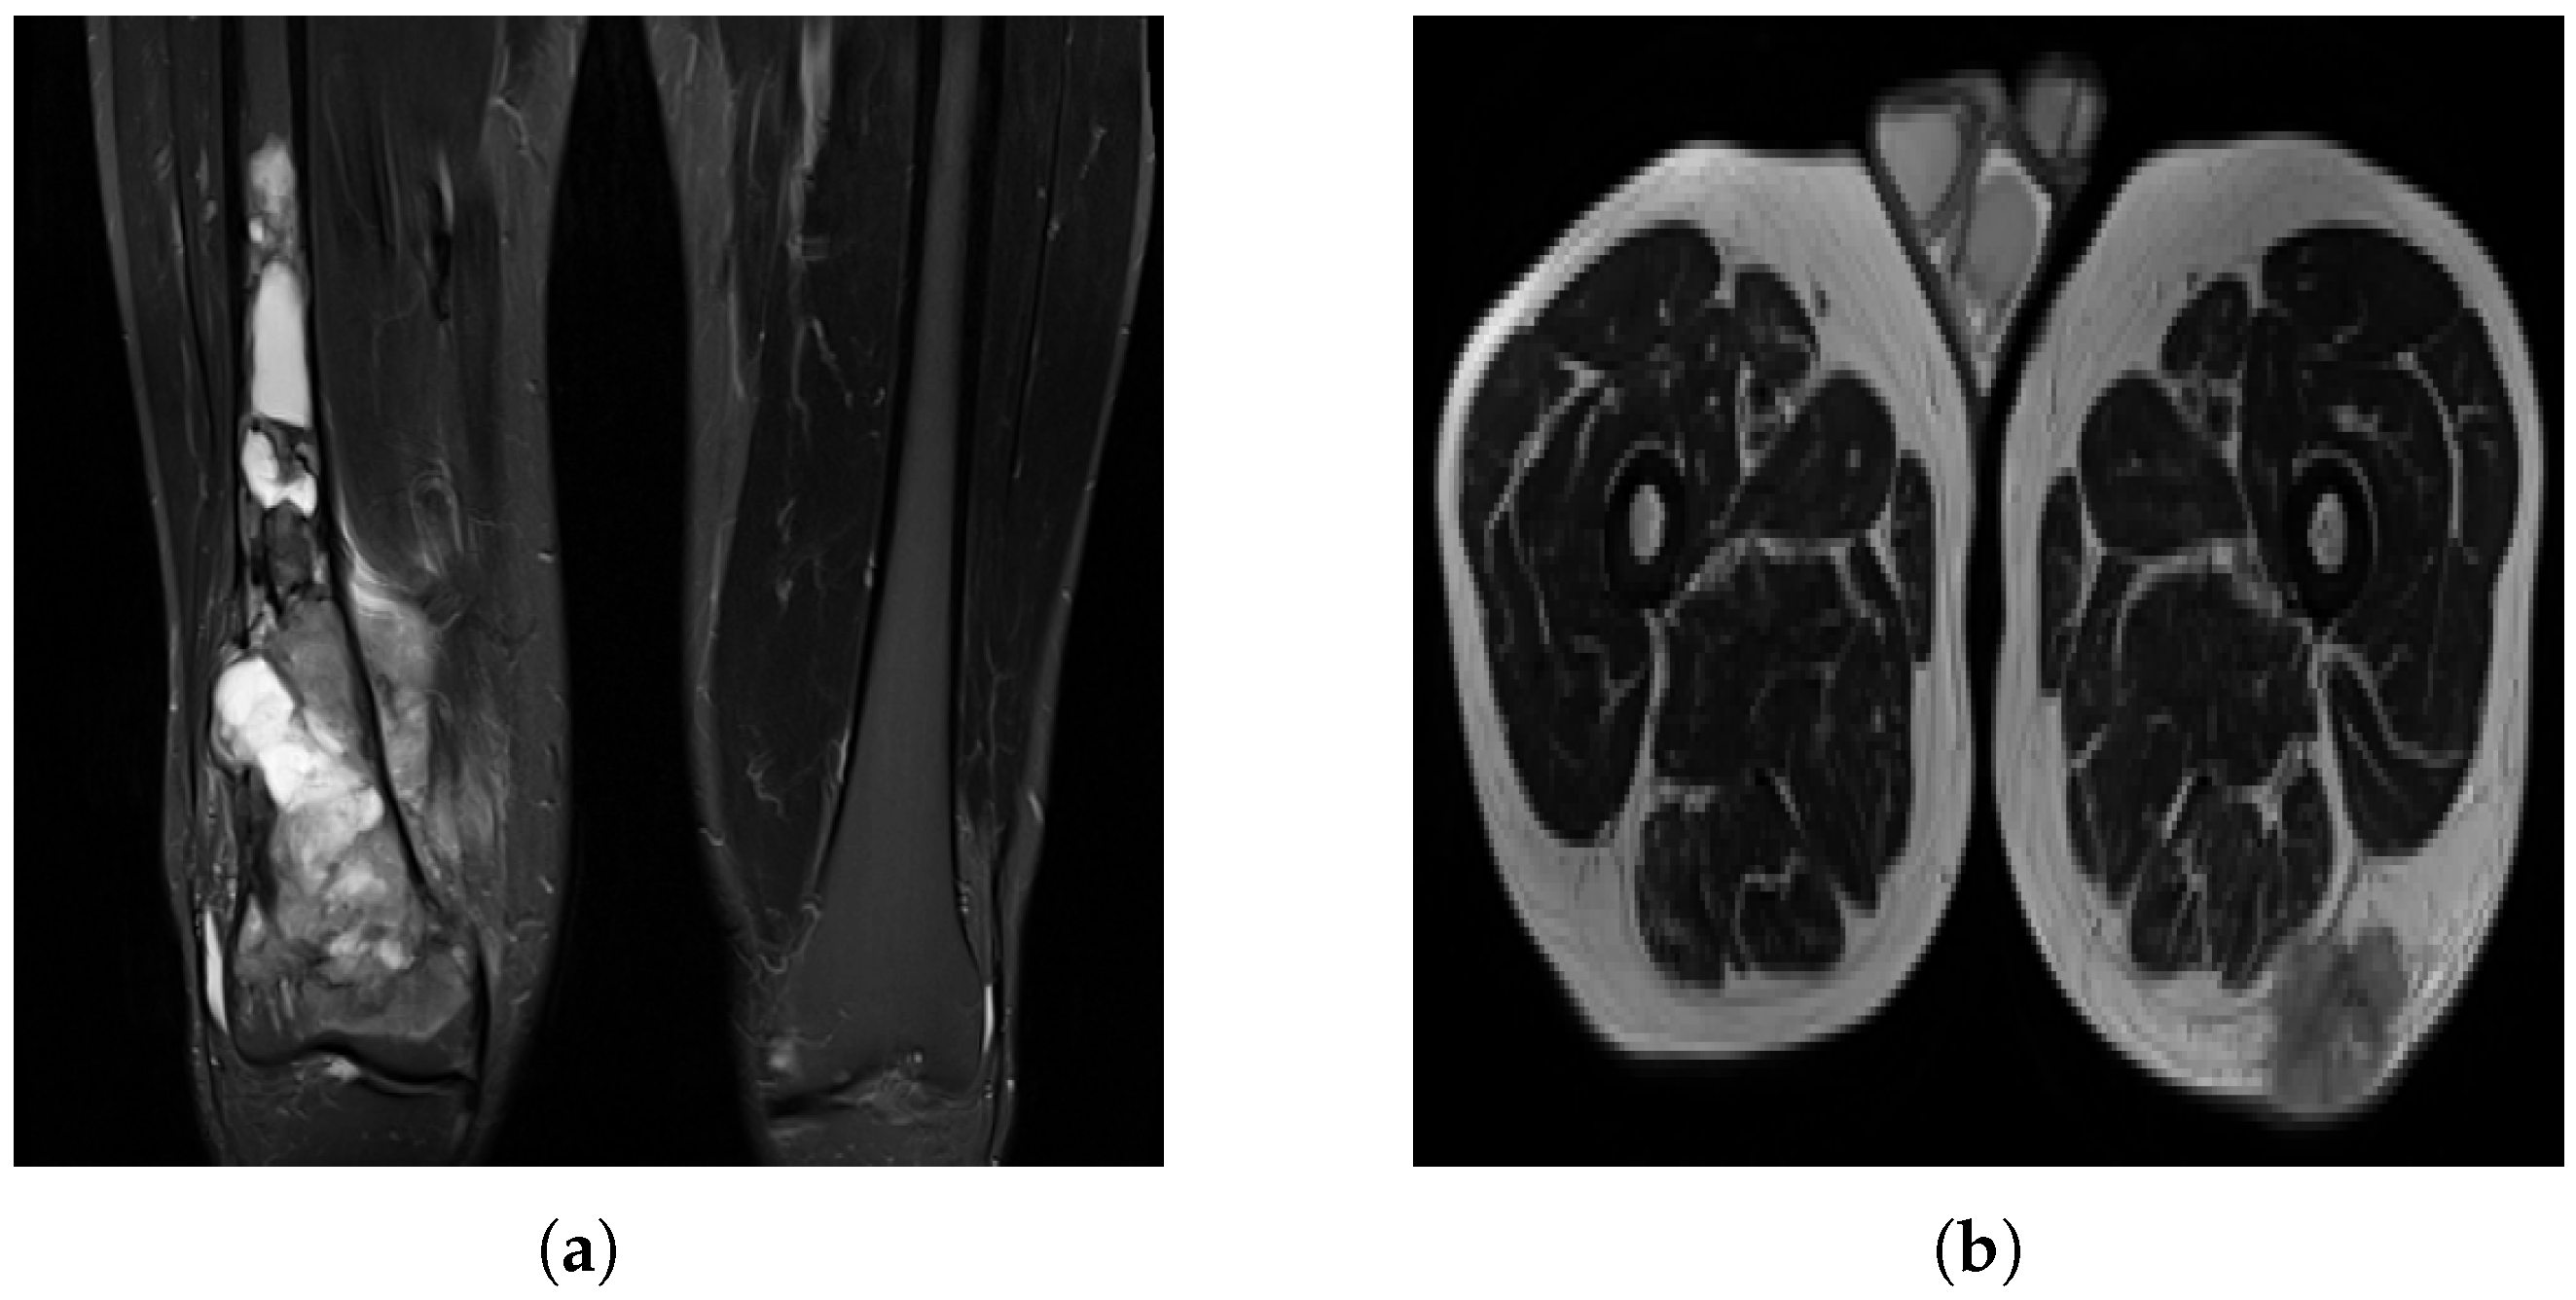

Non-pathological tissue was grouped as healthy, which can cause misclassification, as biological tissue may resemble pathological regions (Figure 4). Small homogeneous regions in segmented 3D images may confuse the model, especially when similar to healthy tissue. Image quality varied significantly between patients (Figure 5), with some images being grainy, blurred or corrupted, which may affect model performance.

Figure 5. Variance in image quality. (a) A grainy slice with relatively high noise. (b) A corrupted image. (c) An example of uneven lighting distribution.